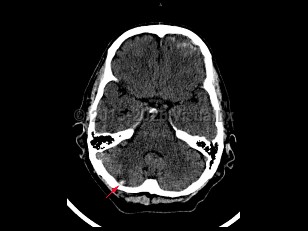

A traumatic injury to the cerebellum occurring when there is forceful contact with the occipital area and surrounding cranium, particularly bony ridges, leading to cerebellar edema and/or punctate hemorrhages. Characterized by dizziness, drowsiness, dysarthria, ataxia, loss of consciousness, and coma. Other signs and symptoms include fatigue, malaise, nystagmus, vertigo, and mydriasis. Associated with basilar skull fracture, cerebellar hemorrhage, traumatic hematoma, subarachnoid hemorrhage, and traumatic brain injury.

Management includes careful assessment and monitoring of symptoms and level of consciousness, mindful that there can be delayed deterioration after cerebellar contusion, which increases risk for complications and death following brain trauma. Wide craniectomy and internal decompression may be advised.